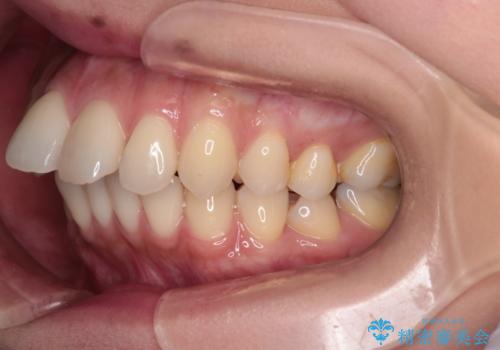

- 上の前歯の突出感を気にして来院された患者様です。

目立たない装置を希望とのことで、上顎左右第一小臼歯を抜歯し、インビザラインにて矯正治療を行うこととしました。

インビザラインにて抜歯矯正を行うと、高頻度で奥歯が咬み合わなくなります。

また、抜歯スペースに向けて奥歯が移動する際、必ず傾斜して移動するため、仕上がりの咬み合わせはワイヤー矯正と比べて明らかに劣ります。

抜歯スペースが閉じてからも咬みにくさ改善のためマウスピース矯正を継続するため、治療期間は長期化します。